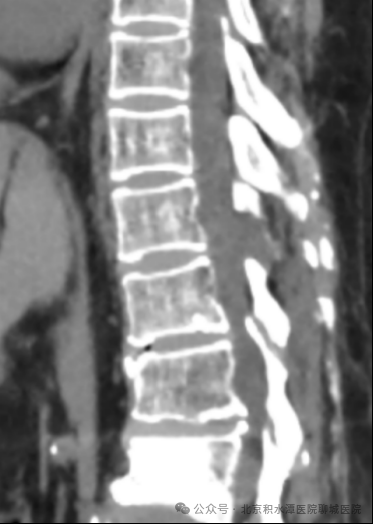

术前影像:T11/12胸椎黄韧带骨化,胸椎椎管狭窄

术后影像:去除少量骨质扩大胸椎椎管

并取出骨化的黄韧带